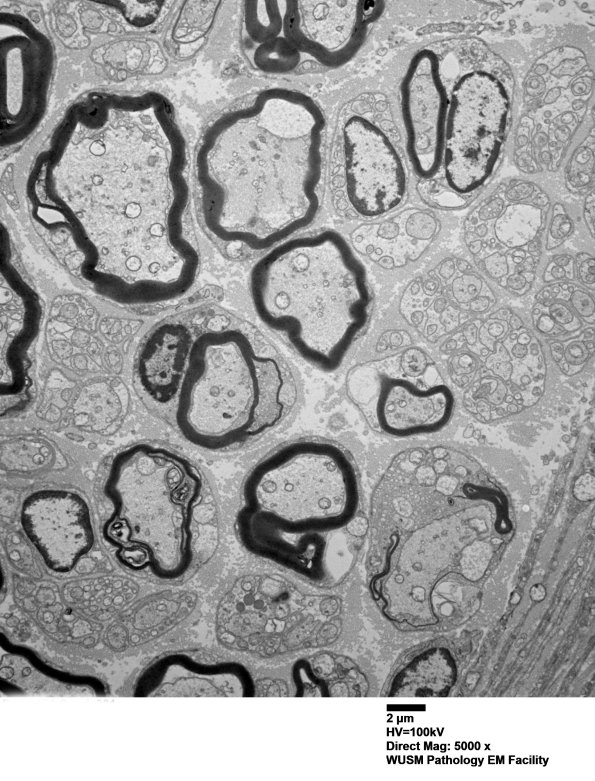

4B1-4 In this individual there are significant populations of both large and small myelinated axons as well as pale pre-myelinated axons. (electron micrograph)